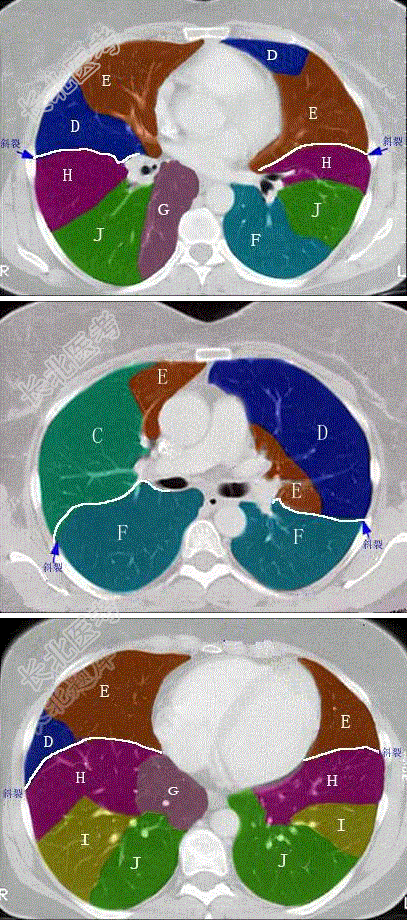

- 单项选择题结合肺段模式图,选出右肺下叶的组成

A、F

B、F+G

C、F+G+H

D、F+G+H+I

E、F+G+H+I+J